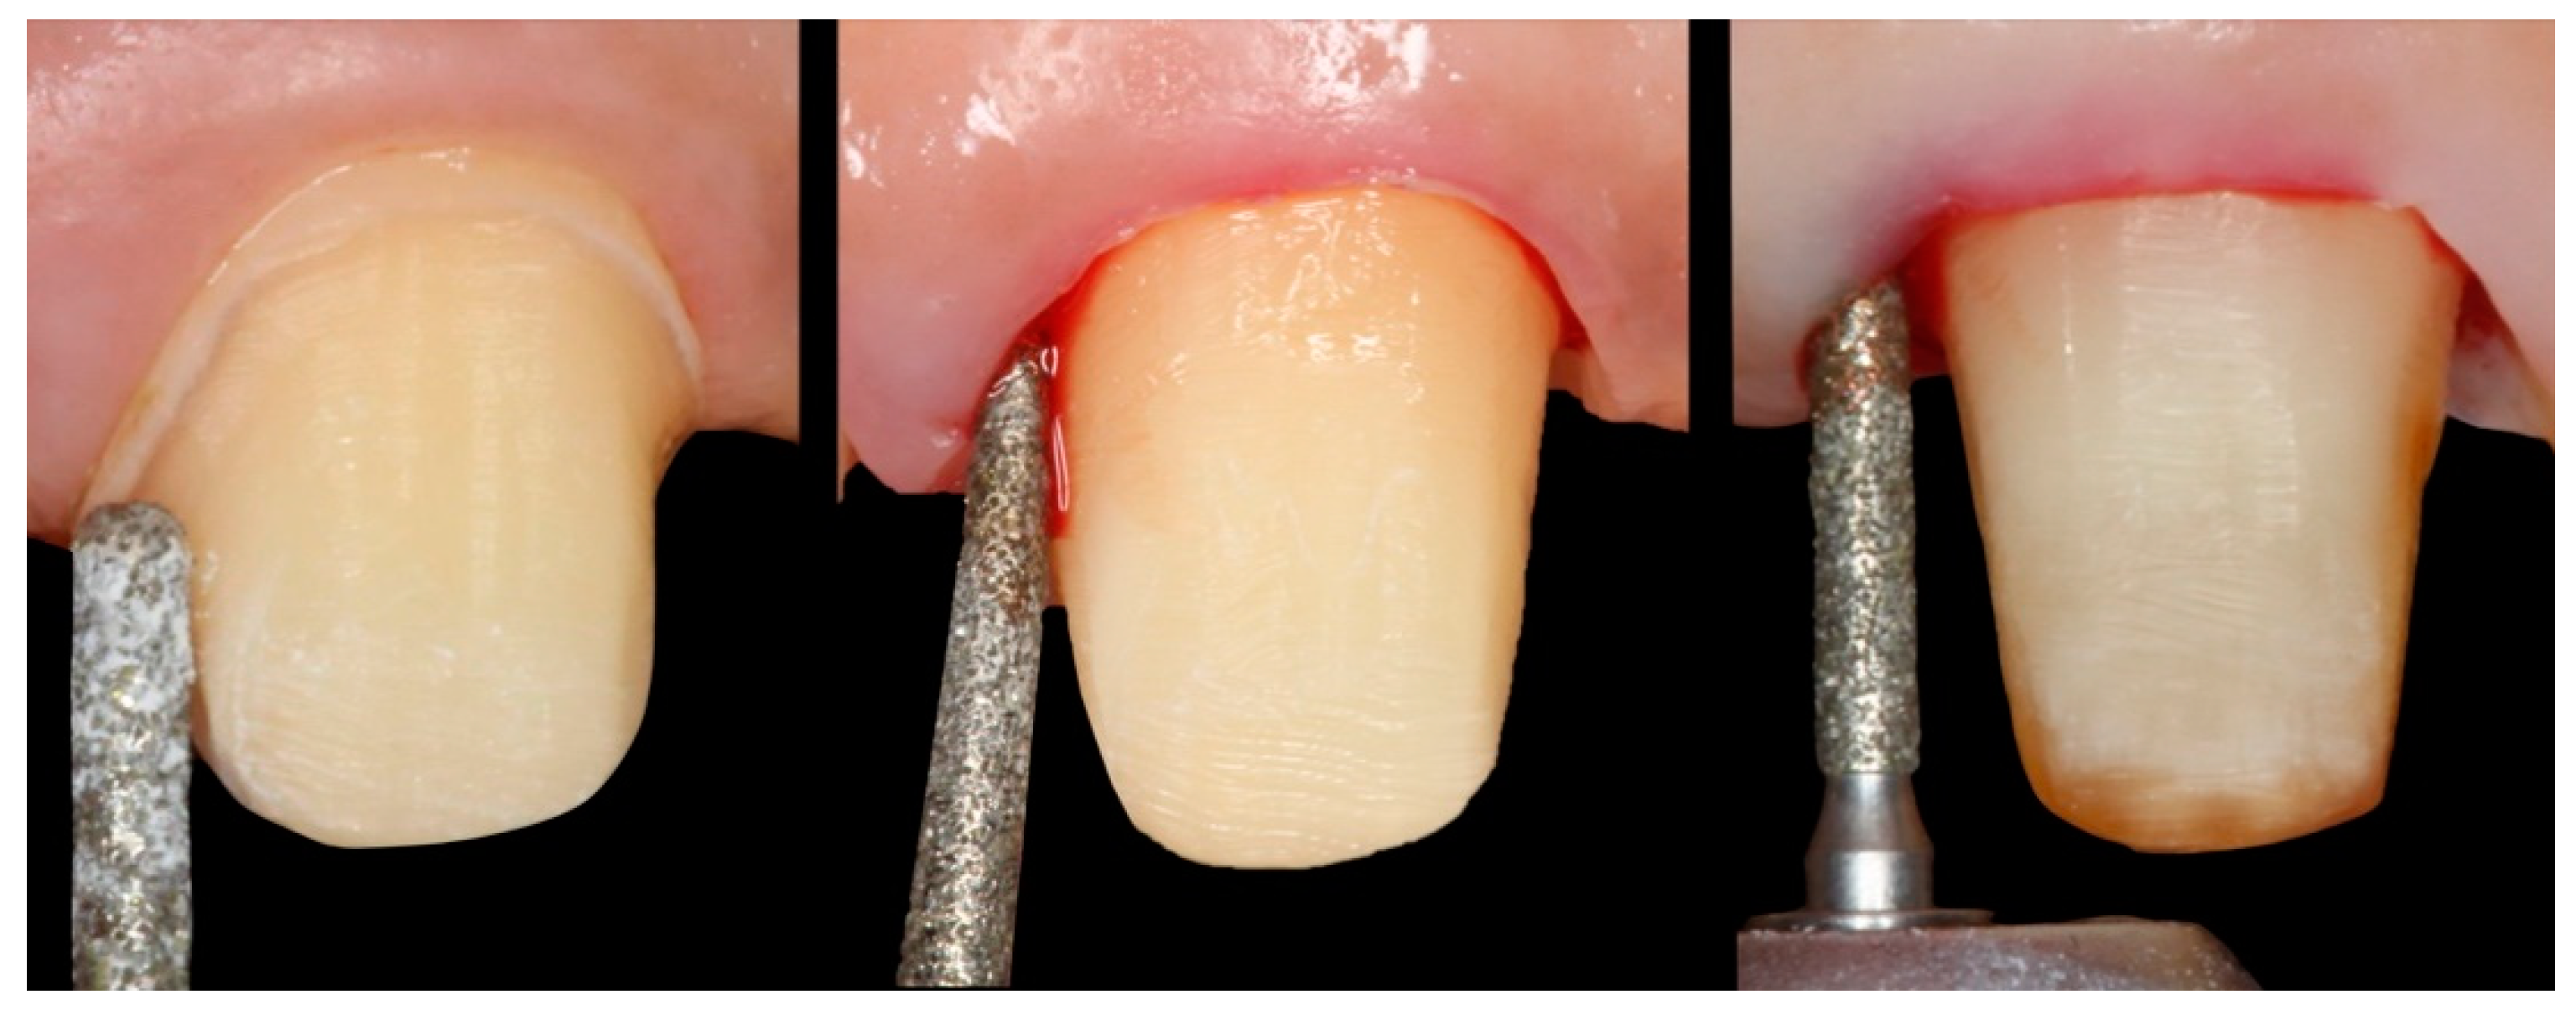

A total of 31 previous restorations were withdrawn (incisives and upper canines), one for each patient, and these teeth were prepared using BOPT (Figure 1 and Figure 2) [6]. The clinical sequence for BOPT was as follows: Before the removal of the old restorations, double probing (gingival sulcus probing and bone probing) was performed to determine the preparation limit and to situate the location of the provisional restoration (0.5–0.8 mm below the edge of the gingiva) so as not to invade the supracrestal attached tissue. After the removal of the old restorations, BOPT preparation eliminated the pre-existing finish line using a turbine and 100/200 μm cone diamond bur with a 1.2 mm diameter (862.534.012, BOPT drills; Sweden and Martina, Due Carrere, Padua, Italy). For realization of the BOPT preparation technique, the bur was first introduced with an angulation of 10–15° with respect to the dental axis. This first step aimed to open the dental groove and eliminate the first millimetre of the emergence of the anatomic crown. In the second step, the bur was introduced parallel to the dental axis in order to eliminate the pre-existing finish line. In the third and final step, the bur was introduced at a 3–6° angle with respect to the dental axis to give it the necessary convergence (Figure 3). Afterwards, in accordance with the protocol guidelines, a provisional crown was made in the clinic for each tooth with self-polymerizing acrylic resin (Sintodent, Sintodent s.r.l., Roma Italy) with an approximate angle of 45°. The provisional prosthesis created a new cement–enamel–prosthetic junction situated in the gingival sulcus at a depth of 0.5–0.8 mm, with consideration of the biological width. Provisional restorations were not removed until the soft tissues had completely matured—a period of 8–12 weeks.

Figure 1. (a) Tooth with a chamfer finishing line. (b,c) tooth being prepared with the BOPT technique.